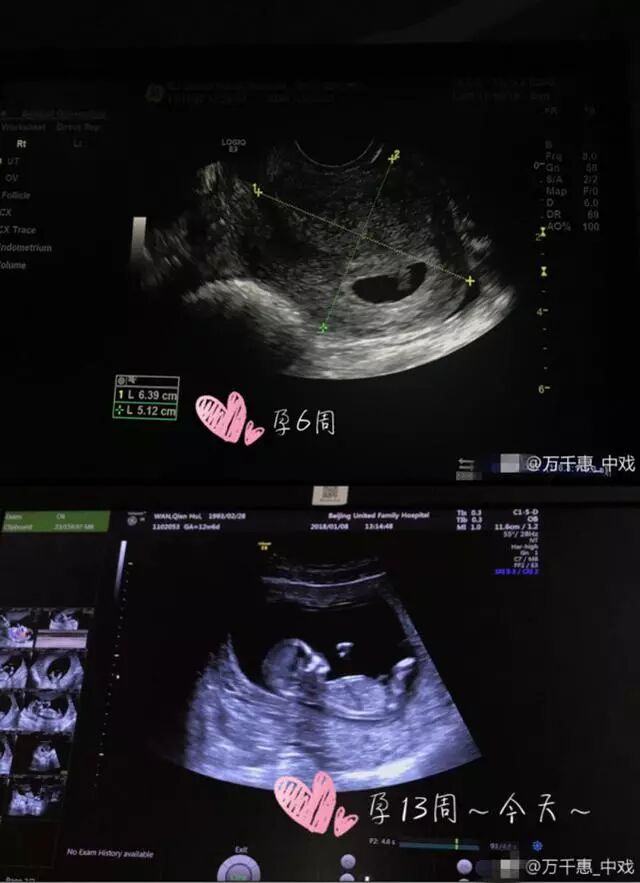

1月8日下午,三宝小25岁娇妻万千惠在微博宣布怀孕喜讯,不仅如此,万千惠还详述了从结婚到怀孕的心路历程,字字真情令人感动不已。升级为准妈妈的她还大方晒出了宝宝的B超照片和网友分享,喜悦之情溢于言表。

“2017~我不平凡的本命年,2月领证,6月结婚,10月有了新生命~~一切都顺其自然,按部就班,开花结果(来自妈妈的PS:今天终于满12周了,去做了第一次正式产检,小家伙一直在蹦,不停蹦太不老实了!有动图为证NT顺利通过,感恩!希望你健康长大!7月份见,爱你)”万千惠微博中写道。从万千惠的发文中不难看出其激动的心情,字里行间也母爱满满。

万千惠晒出的B超照。万千惠和三宝于去年6月举办婚礼,虽然两人有25岁的年龄差,但这并不影响二人的感情。夫妻俩经常毫不避讳地在人前秀恩爱,幸福之情羡煞旁人。